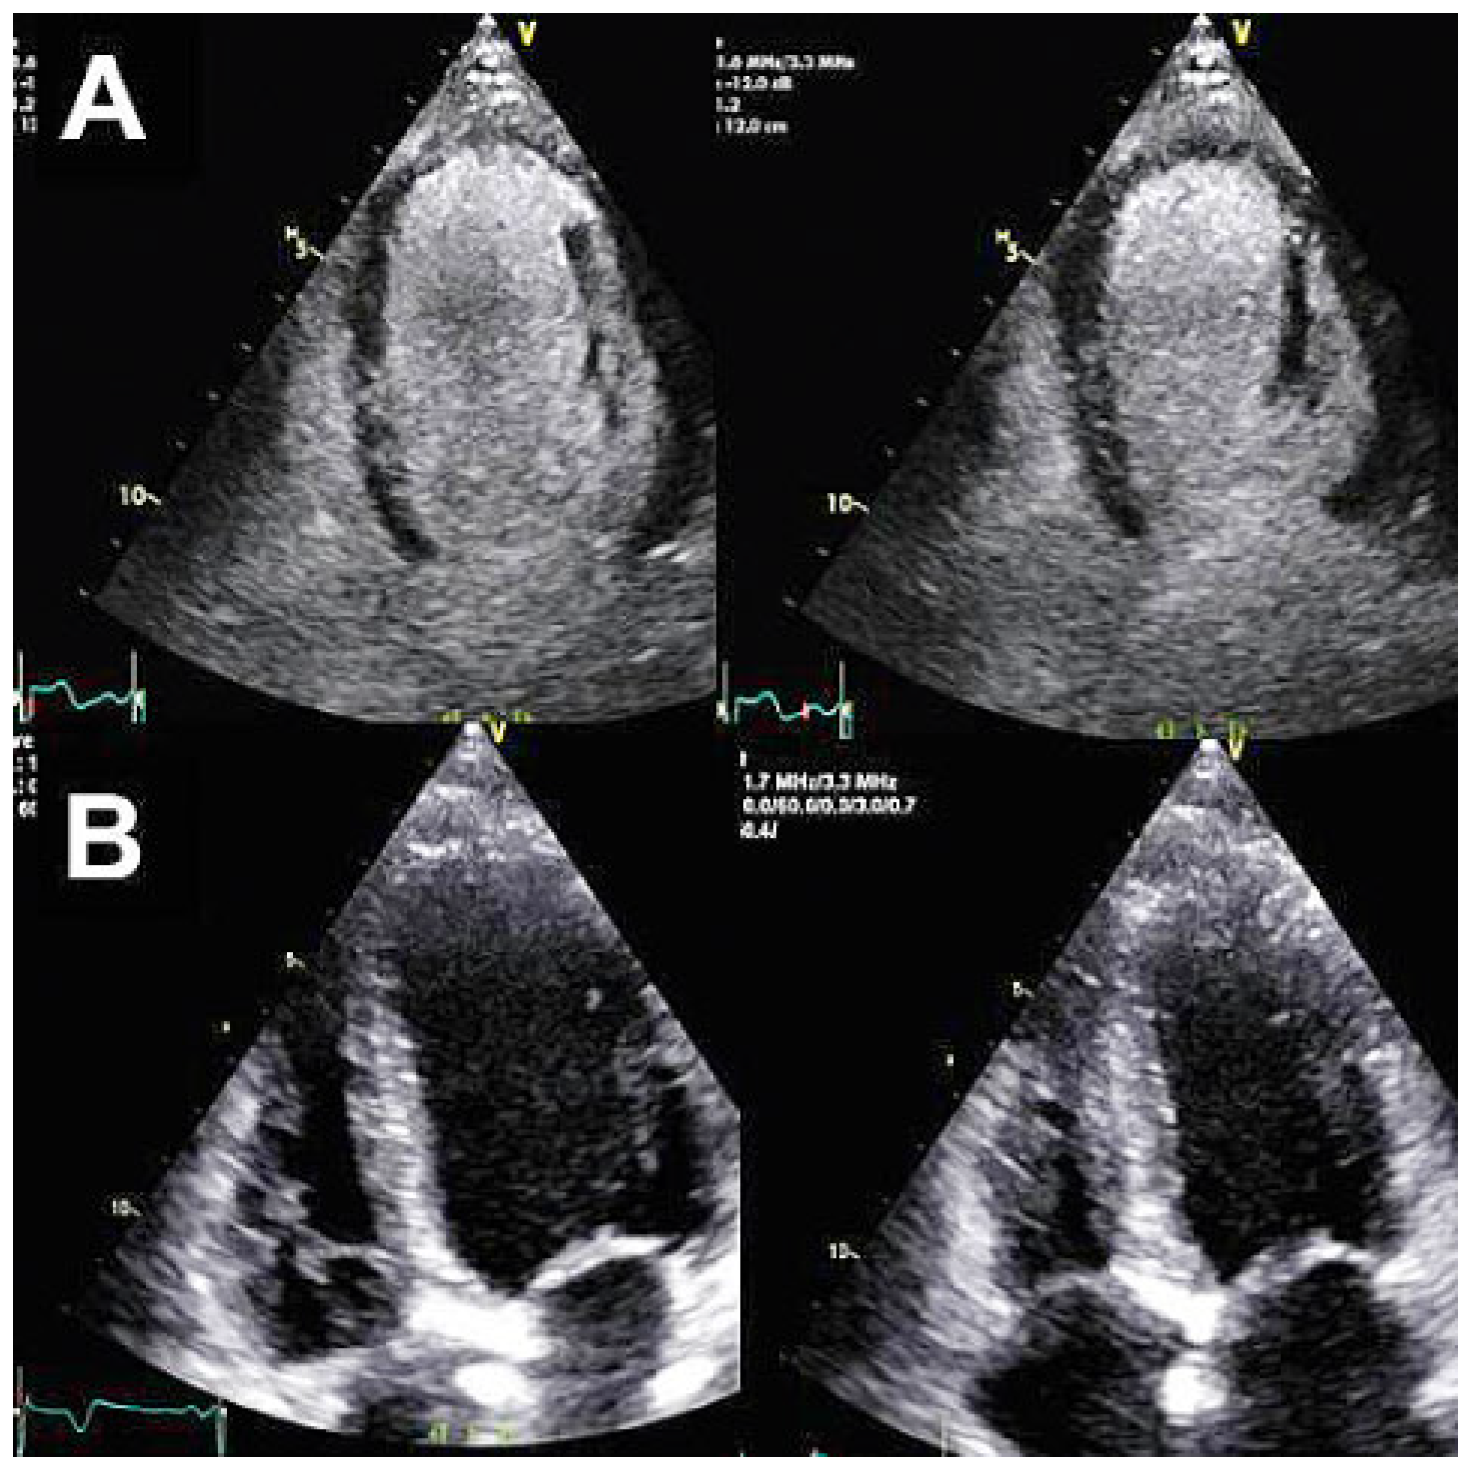

Methods: A boy at the age of two years and 5 months was referred to our hospital because of the presence of a severe aortic regurgitation (AR) associated with sub-aortic membrane. Two years ago, at the age of 5 months, he was operated in another centre for ASO and VSD closure for d- transposition of great arteries (D-TGA) with ventricular septal defect (VSD). Echocardiography (Figure 1) showed a thickened aortic neo-valve with severe eccentric regurgitation with diastolic reflux of the descending aorta. A cardiac CT was performed and showed very tortuous thoracic aorta and discreet stretching of the pulmonary arteries with a mass aspect due to the LeCompte maneuver. The thoracic aorta appearing “crushed” by the LeCompte maneuver.

Results: Redo sternotomy was performed, the heart and great vessels were dissected and exposed. Under the CPB, neo-pulmonary root was transected (pulmonary root was on anterior after the LeCompte maneuver), aorta was clamped and selective cardioplegia was administrated. We note a retracted and shortened anterior leaflet caused by VSD patch. Other two leaflets were normal. After the resection of the anterior leaflet and sub-aortic membrane, we started the aortic valve reconstruction. The distance between commissures was measured with special Ozaki sizing device. Because of the missing of the autologous pericardium, we used a CardioCel® patch (bovine pericardium). The size corresponding to the measured value was cut. The annular margin of the patch leaflet was sutured with 5-0 Prolen running sutures to the annulus. Commissural coaptation was secured with additional 5-0 Prolen sutures. The aortotomy was closed. Intraoperative echocardiography showed an excellent result.